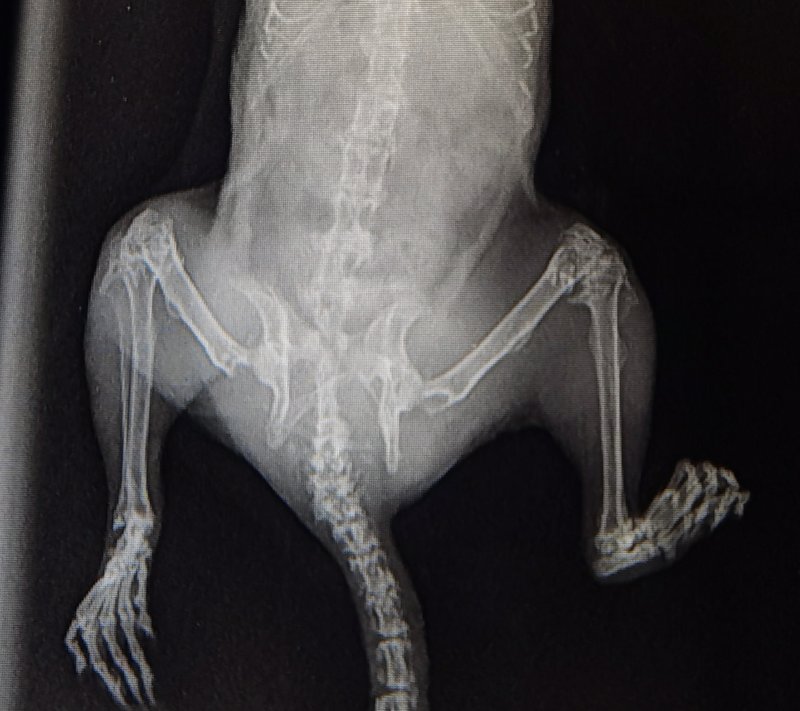

я вижу немного другое. Вот дегу Юли, это нормальные косточки и снимок Вашего дегу, обратите внимание на косточки задних лап, те, которые на Вашем снимке выделены кружочками

на снимках Вашего дегу идёт распад надкостницы и перерождение структур коленных суставов. Мелоксикам, да, видимо пожизненно, проблем с сердцем на таком снимке не видно. В Вашем случае я бы ещё добавила витамин Д по 1 капле 2 раза в неделю и хондроитин или аналоги, типа ГХК, 1\6 или 1\8 таблетки, но не факт что поможет....

давайте ближе посмотрите, что с косточками произошло

он не слабые, они перерождаются, по типу "остеопороза", также известный как потеря костной массы, который является метаболическим заболеванием скелета, при нём кости теряют свою нормальную структуру. Они становятся пористыми и хрупкими. Заболевание протекает на первых порах бессимптомно.

возможно по типу накопительного эффекта-было плохо, но не так, потом начались проблемы с иннервацией и ещё посмотрите на структуру позвонков в хвостике, там тоже полная деструкция , то же самое может быть и с позвонками в поясницы, а это будет ущемлять нервные окончания задних лапок и хвоста